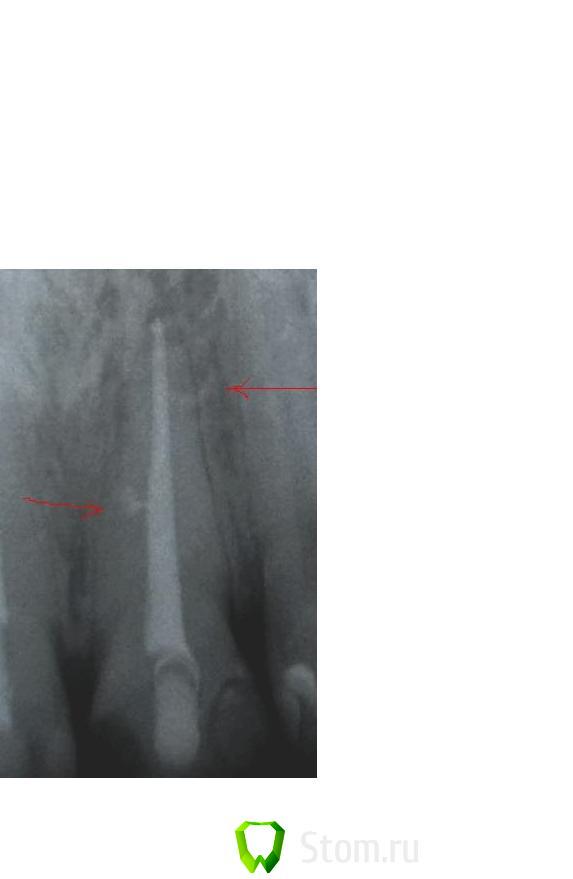

SanyaDok Опубликовано 3 февраля, 2012 Поделиться Опубликовано 3 февраля, 2012 (изменено) Эндометазон при хорошей конденсации гуттаперчи не так_уж и плох.Врядли на представленных снимках он рассасется в канале(Имхо).Изв. за плохое качество снимков(телефон) Изменено 3 февраля, 2012 пользователем SanyaDok Ссылка на комментарий

SanyaDok Опубликовано 3 февраля, 2012 Поделиться Опубликовано 3 февраля, 2012 (изменено) Снимка,к сожалению,нет.Эти фотки просто попались под руку(что было...)По памяти где-то до №40,но форма каналлов не идеально круглая,а произв.формы(дистальный щелевидний по-моему)по-этому много щифтов и пошло,В принципе можно сравнить с последним фото (21,11) там пошло много штифтов.Ну,приблизительно так_в каналле разработанном последним файлом №40 ляжет еще 3-4 №30.Короче,дело случая-сколько можно уплотнить_уплотняю,штифты особо не считаю.Я не большой спец-делаю,как мне кажется,правильно...Вот нашел еще один подобный снимок(это не окончательный снимок-медиальные к/к еще допломбировывались.Пометки со снимка убрать не могу)-когда легло много штифтов.Опять-же-фото изначально с телефона,качество плохое. Изменено 3 февраля, 2012 пользователем SanyaDok Ссылка на комментарий

Kivilgar Опубликовано 3 февраля, 2012 Поделиться Опубликовано 3 февраля, 2012 Нормальное количество штифтов. Что-то уж очень много штифтов.Ничего не много, даже мало. Ссылка на комментарий